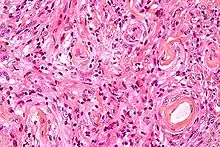

Histologically, meningioma cells are relatively uniform, with a tendency to encircle one another, forming whorls and psammoma bodies (laminated calcific concretions).[18] As such, they also have a tendency to calcify and are highly vascularized.

Meningiomas arise from arachnoidal cap cells,[16] most of which are near the vicinity of the venous sinuses, and this is the site of greatest prevalence for meningioma formation. Some subtypes may arise from the pial cap cells that migrate during the development together with blood vessels into the brain parenchyma.[17] They most frequently are attached to the dura over the superior parasagittal surface of frontal and parietal lobes, along the sphenoid ridge, in the olfactory grooves, the sylvian region, superior cerebellum along the falx cerebri, cerebellopontine angle, and the spinal cord. The tumor is usually gray, well-circumscribed, and takes on the form of the space it occupies. They usually are dome-shaped, with the base lying on the dura.